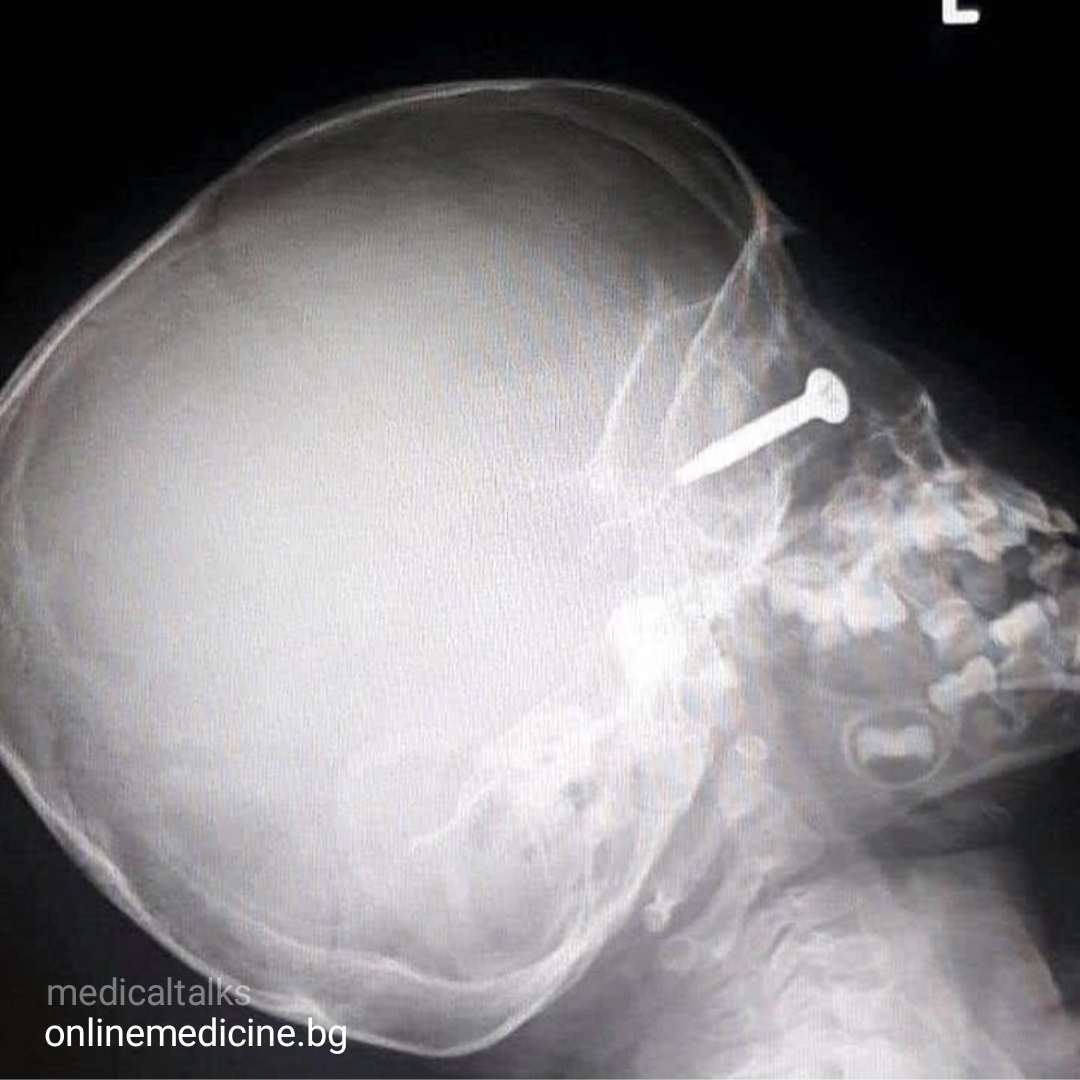

- Рентгенографията разкрива дълбочината, на която е заседнало парчето метал в очната му кухня – достигайки почти до черепа.